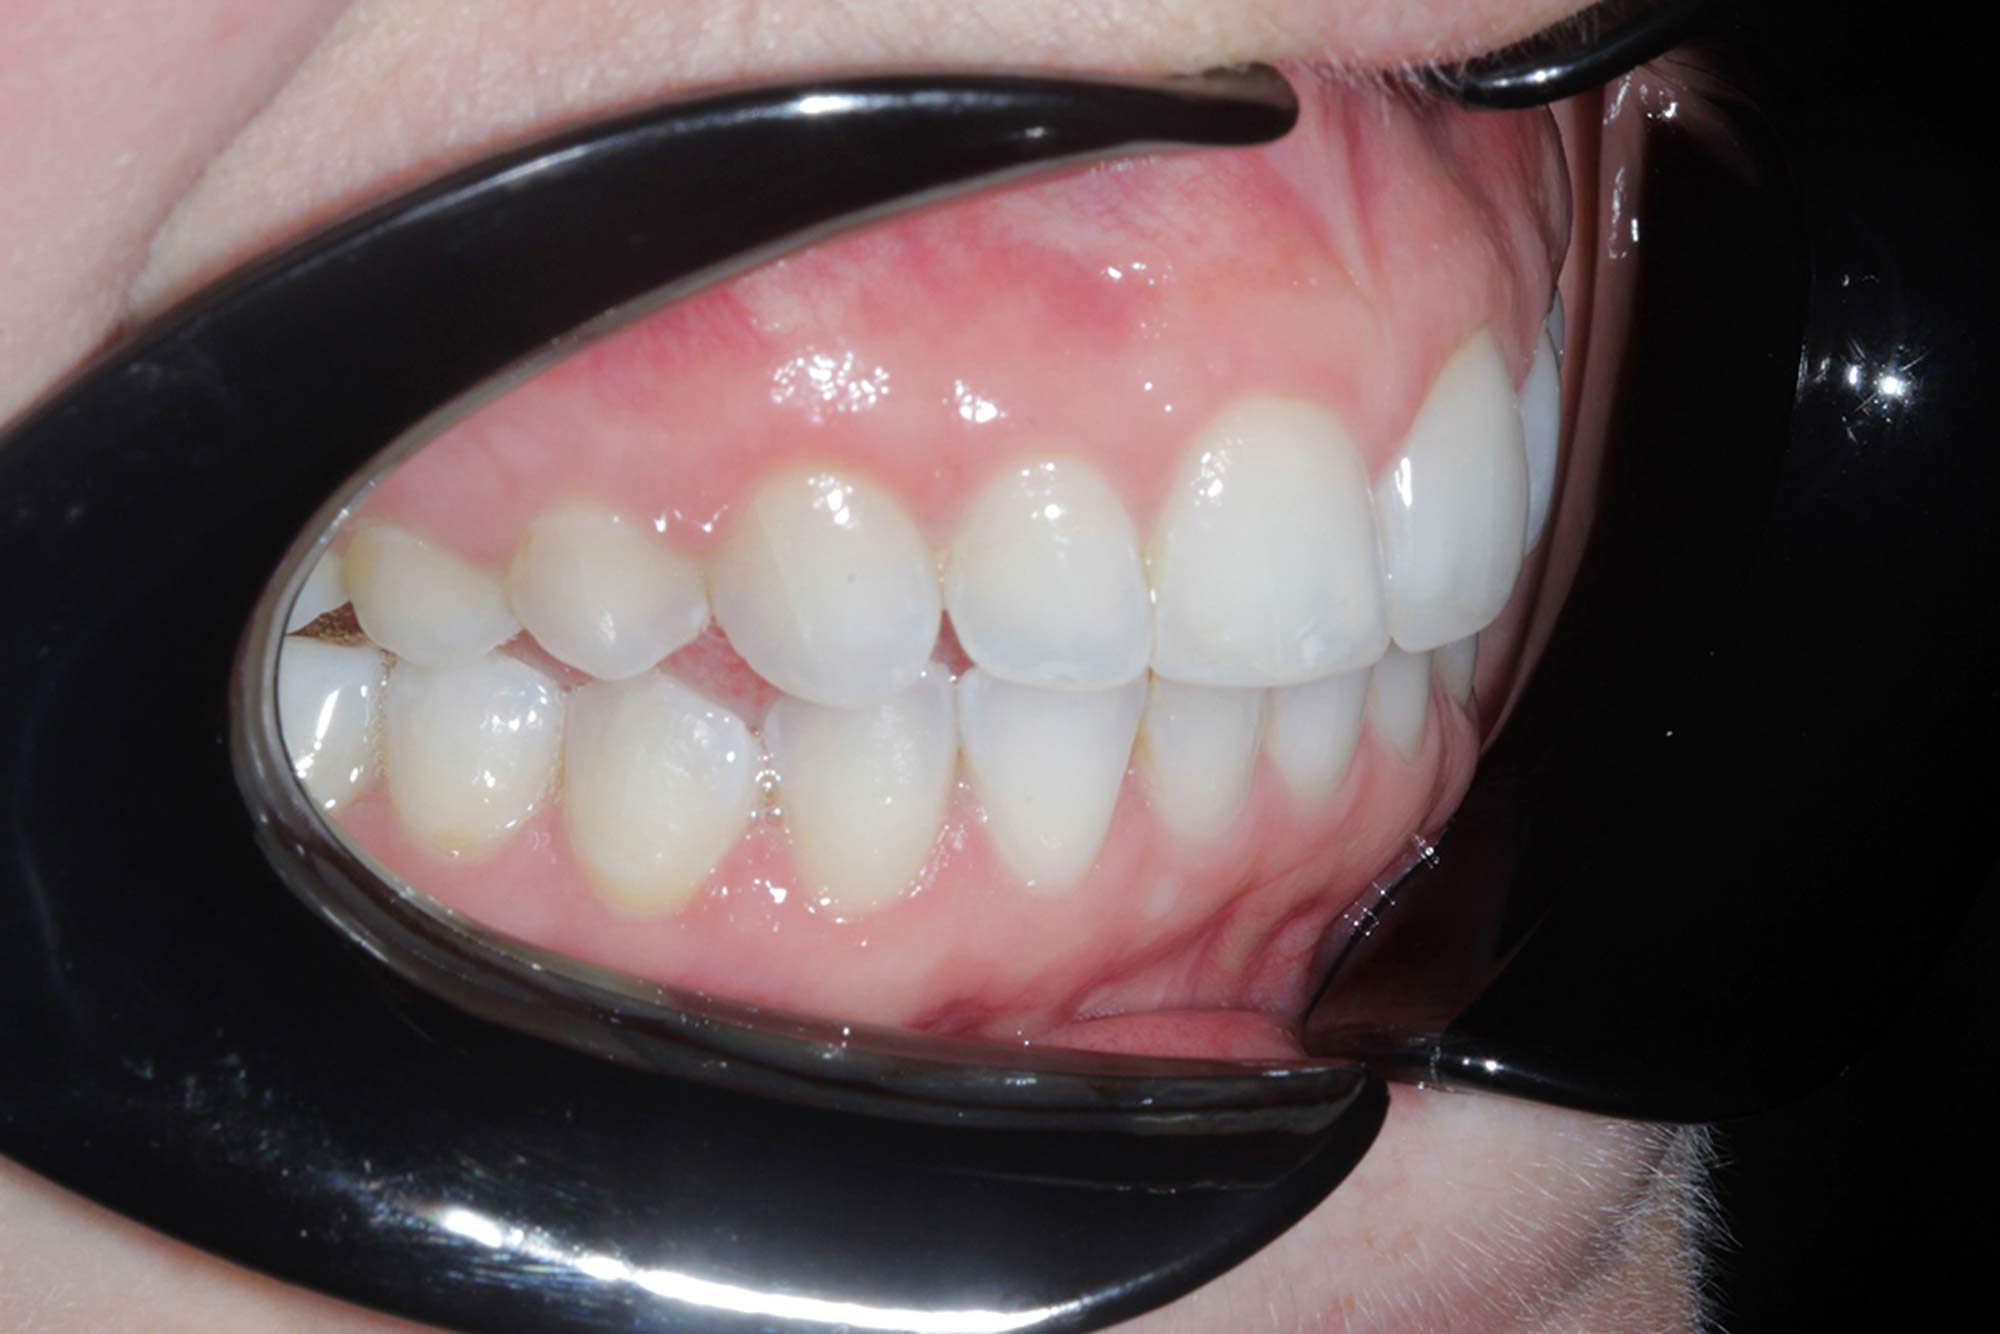

We started off with her aesthetic smile design, as we always do. She had beautiful smile proportions and the potential for perfection was certainly there as we concentrated on matching her gingival margins, widening her buccal corridors and accepting that incisal tooth wear had certainly taken place with some of the edges.

Once we achieved her desired alignment result, the discussion naturally shifted to tooth whitening, and the colour and shade the patient wanted to aim for.

We ultimately achieved a BL1 result, which well exceeded the patient’s expectation.

I achieved this with six weeks of night time whitening, which is fast becoming the norm for those desiring much whiter finishes.

Once the tooth positioning and colour were both at an exemplary stage, it was time to frame the result with composite direct edge bonding. This has been made much easier due to all the other factors. Our restorative material of choice for this case was Venus Pearl shade BL. This matched the patient’s newly whitened teeth perfectly.

The other factors had been carried out to such a high level, that the bonding stage was very straightforward and fairly easy to conduct. Using the right tools to blend the margins in and polish them to give this case even more longevity in the long run. The key to these cases is anatomy. Match the anatomy and proportions, and it will blend beautifully.